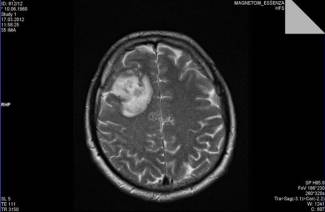

הדמיית תהודה מגנטית היא הכלי החזק ביותר למחקר אבחנות, המאפשר לך להשיג את השלמות והמדויקות ביותר ...